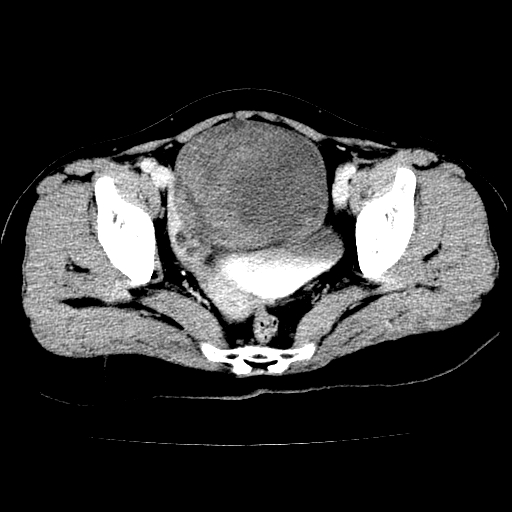

标题: CT24785:女,62岁,发现下腹部肿物半年。 [打印本页]

标题: CT24785:女,62岁,发现下腹部肿物半年。

女,62岁,发现下腹部肿物半年,下腹部不适。

考虑子宫平滑肌肉瘤可能性大。

实性成分太多,要是囊腺瘤也要考虑恶性。